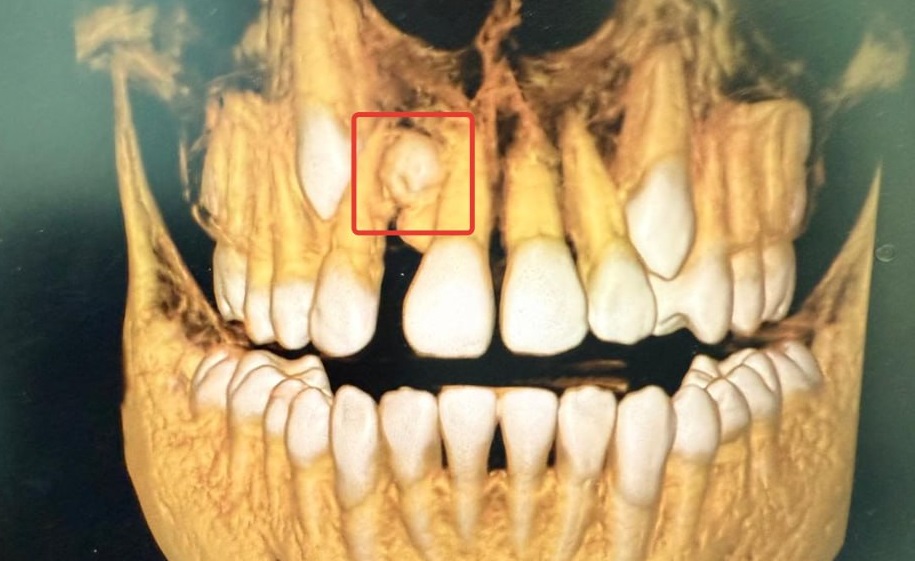

В стоматологической поликлинике № 7 врачи удалили 13-летнему мальчику лишний зуб. Как сообщили в региональном Минздраве, эта аномалия является редкой, по статистике встречается лишь в одном из тысячи случаев.

Ребенок обратился с жалобами на эстетические проблемы. На КТ обнаружили лишний зуб на верхней челюсти, расположенный между центральным и боковым резцом.

«Сверхкомплектные зубы — это аномалия, при которой у человека появляется больше зубов, чем обычно. Она может проявляться как у детей с молочными, так и у взрослых с постоянными зубами», - говорят в министерстве.

Врачи удалили лишний зуб и провели лечение.